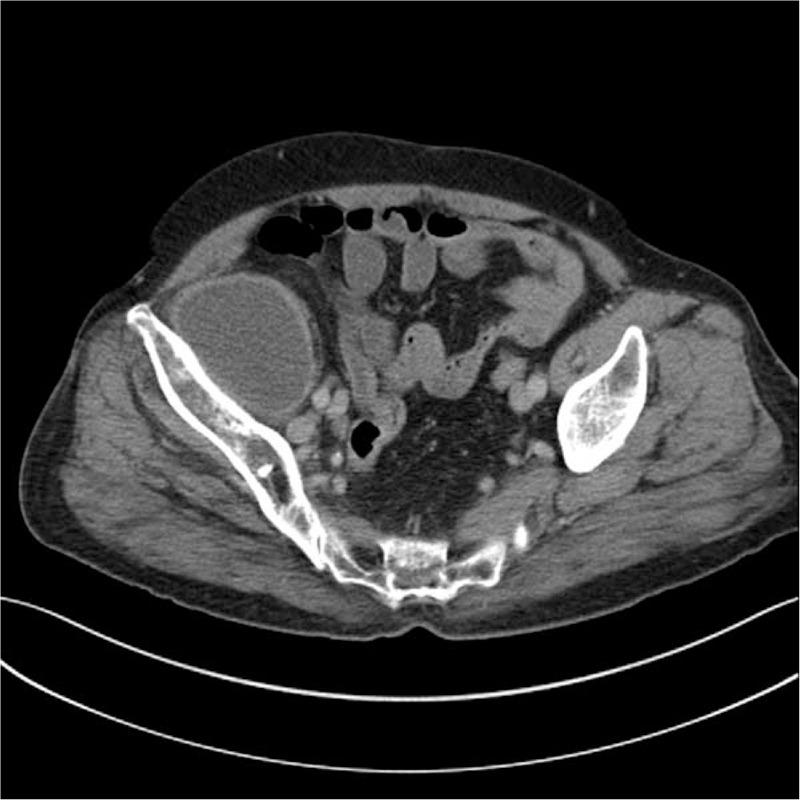

A 70-year-old female was referred to our emergency department due to huge mass in her right pelvic area on abdominal CT. She complained of mild febrile sensation, generalized weakness, and pain in her right leg for several months. The patient underwent metal-on-metal bearing THA 11 years ago for treatment of right-sided hip pain due to avascular necrosis.

一名70岁女性因腹部CT显示右盆腔巨大肿块被转诊至我院急诊科。她主诉数月来有轻微发热感、全身无力及右腿疼痛。该患者11年前因右侧股骨头缺血性坏死导致的髋关节疼痛接受了金属对金属承重表面的THA手术。